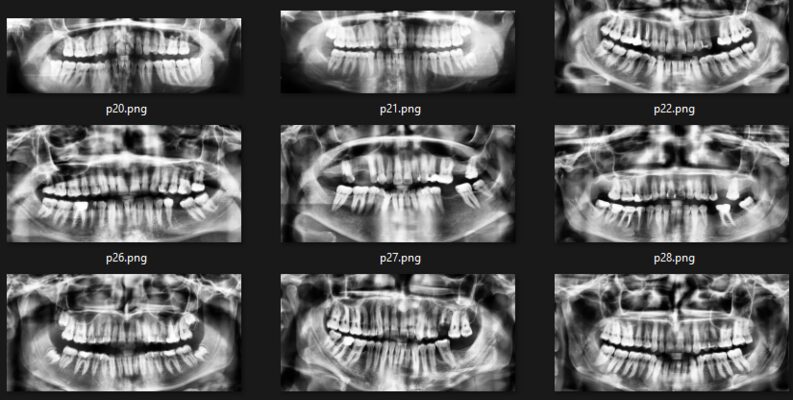

Dental X-ray Images for Analysis 牙科 X 射线图像数据集

该数据集包含各种各样的牙齿正畸断层扫描 (OPG) X 射线图像,包括 70 个高质量样本。通过提供注释,此数据集可用于训练和测试机器学习模型,以进行牙齿类型分类、异常检测等牙科图像分析任务。受新兴计算机视觉领域的启发,并受牙科对改进诊断工具的需求的推动,该数据集旨在使研究人员、从业者和爱好者能够探索创新解决方案,以增强口腔保健效果。